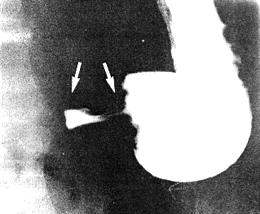

Generally speaking a similar sequence of events was seen in the majority of patients in this group, namely a short hold-up at the pyloric ring, followed by 2 or 3 incomplete (or occasionally maximal) contractions of the pyloric sphincteric cylinder and commencing emptying into the duodenum (Fig. 12.3). The degree of dynamic narrowing of the lumen, as seen radiologically, probably corresponds to the amplitude as measured manometrically. This varied greatly among subjects.

![]() |

| Fig. 12.3. The first of two or three maximal contractions of pyloric sphincteric cylinder (arrows) preceding emptying into duodenum |